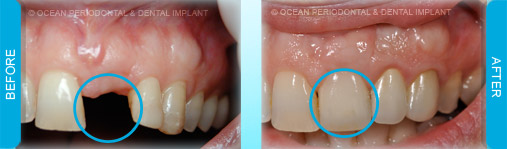

Dental implants are commonly used to replace missing or lost teeth in order to ensure patient comfort, function, and aesthetics. Indeed, there are many treatment options for management of missing teeth, such as bridges, and partial/complete dentures.

Nonetheless, numerous studies have demonstrated that implant-supported restorations are generally deemed to have superior functional and aesthetic outcomes. Furthermore, there are cases where dental implants may be the only logical choice for the restoration of function and aesthetics.

Dental implants can be used to replace missing teeth. There are many benefits to this type of treatment.